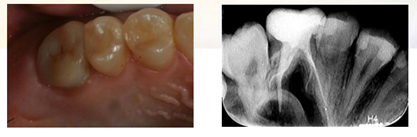

牙体预备制取26高嵌体工作模型

复诊,无不适,上橡皮障,粘接树脂高嵌体

三个月复查